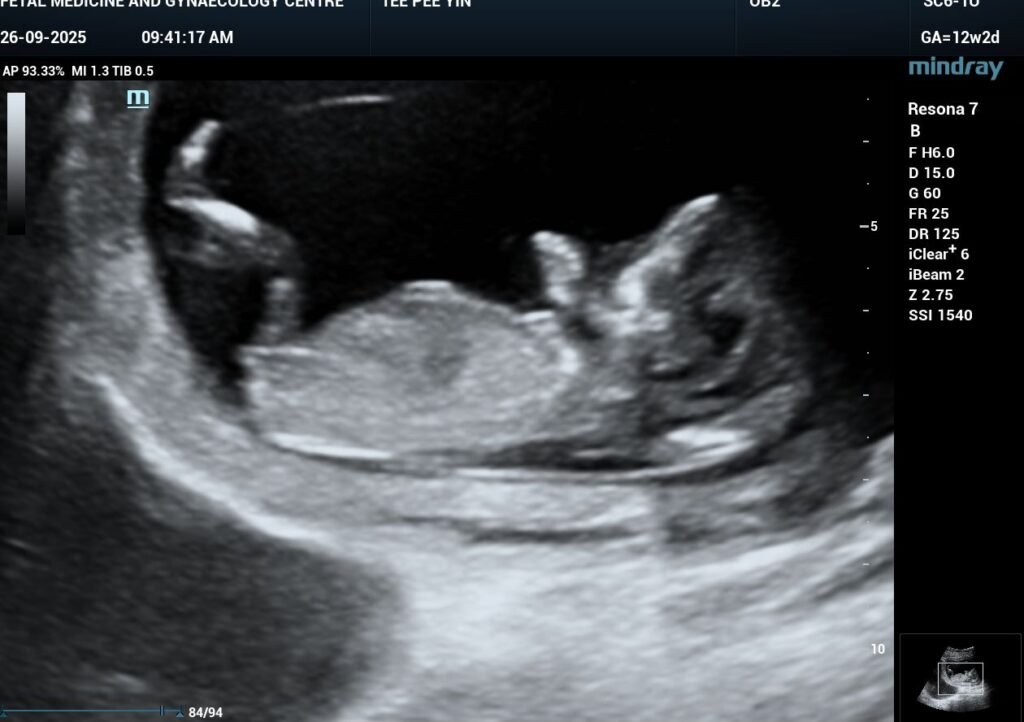

Within three months, her period became regular again, her sleep improved, and she felt calmer and lighter. In August 2025, Ms. T found out she was naturally pregnant.